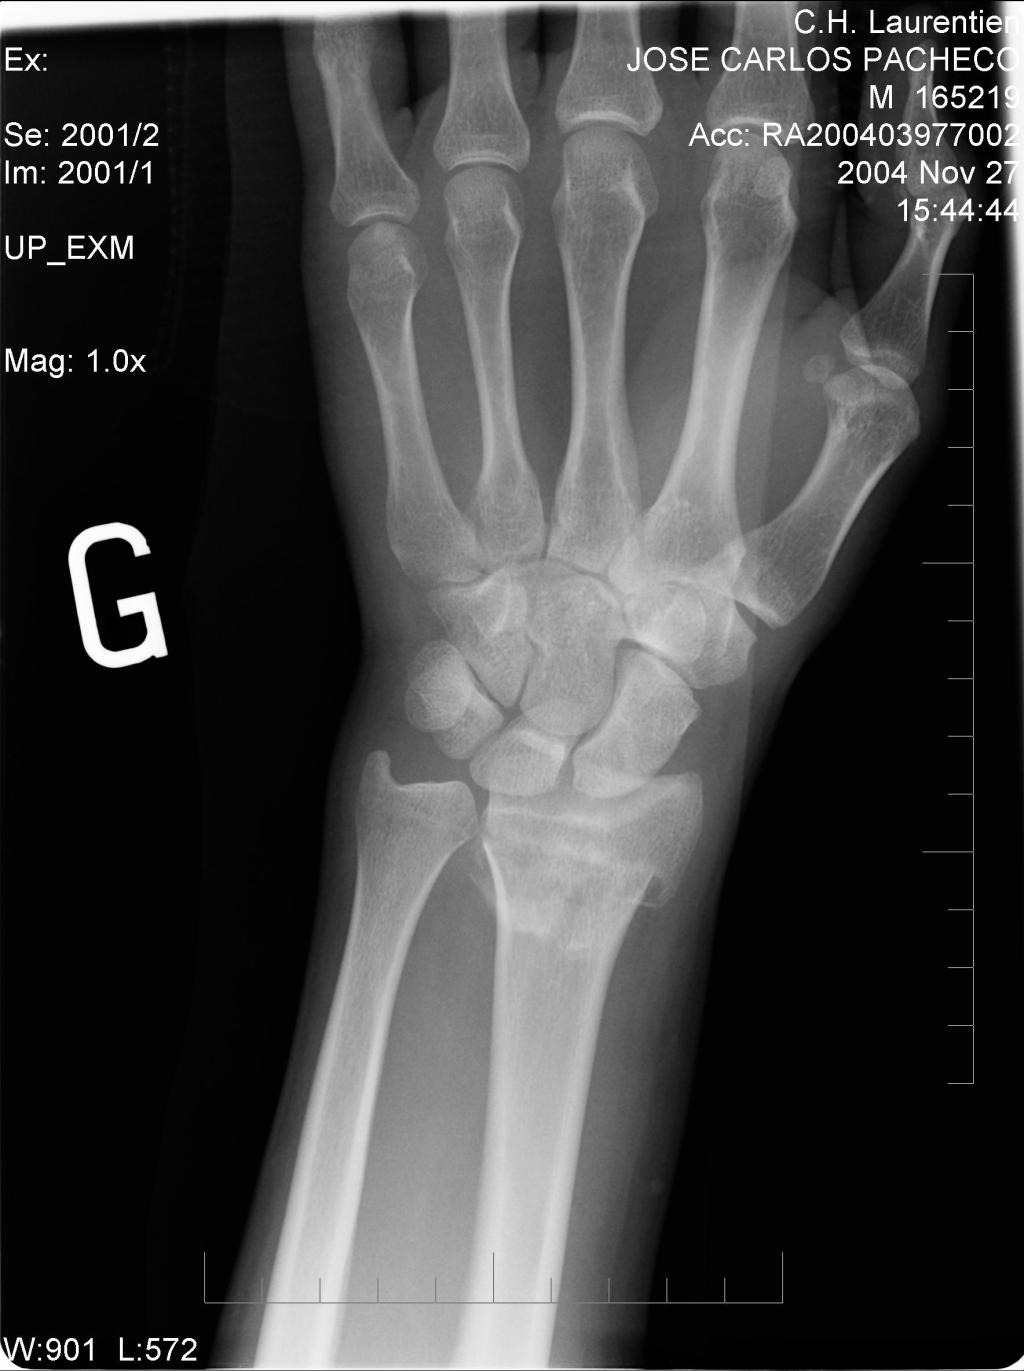

TENOLISI E FRATTURA DI RADIO, CHE LEGAME C’E’?

Dopo la lunga pausa estiva riprendiamo con i nostri spunti di riflessione in ambito di salute. Visto il grande interesse nei confronti dell’intervento di tenolisi vi voglio parlare dell’ultimo caso che ho trattato. In questa occasione la problematica si è presentata dopo una frattura di radio trattata con gesso, già durante il periodo di immobilizzazione…